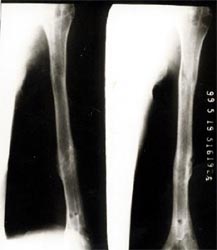

图1-2 骨折在12个月后愈合,功能恢复满意。